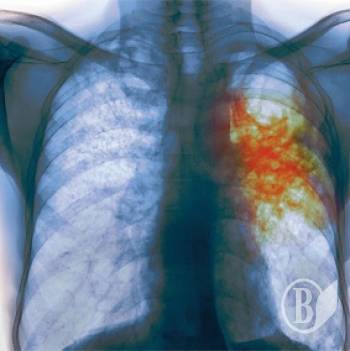

Одна із виховательок чернігівського дитсадка №22 виявилася хворою на відкриту форму туберкульозу.

«А у травні вона виявилася хворою відкритою формою туберкульозу, хоча ця стадія триває від 6 до 10 місяців. Лікарі ж на зборах запевняли, що вона тільки-но захворіла» - пише Вікторія Пискун.

Усім вихованцям дитсадка призначили зробити проби Манту, тим, хто тісно контактував з хворою вихователькою – зроблять флоорографію.